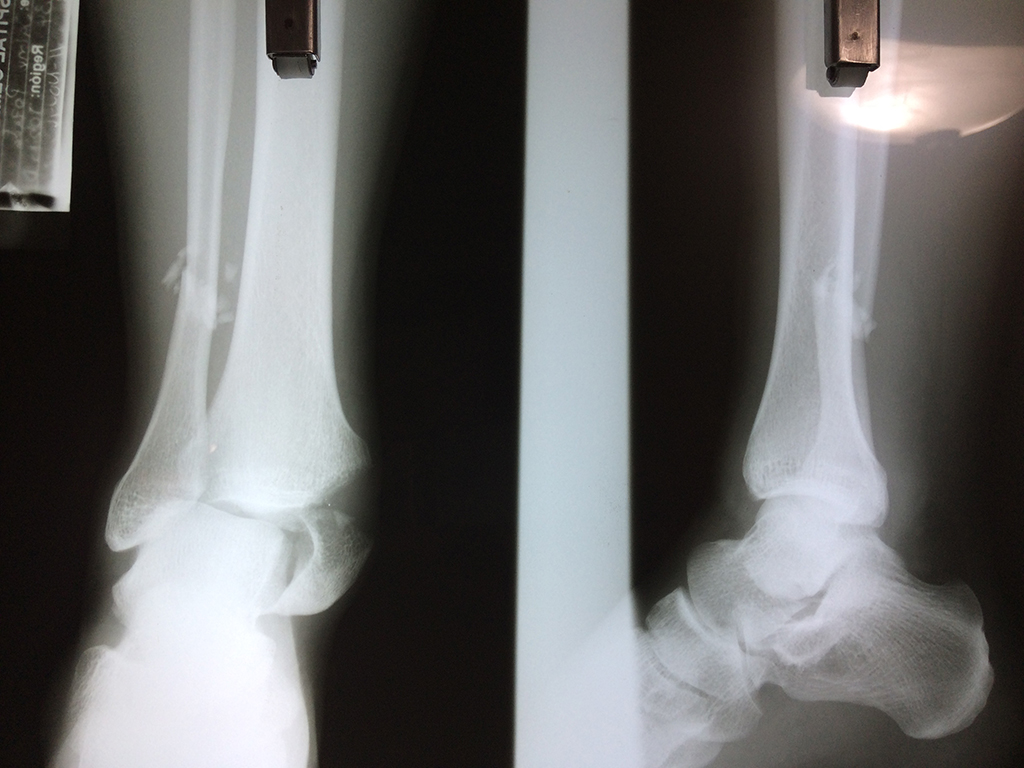

Una fractura de tobillo es la rotura de uno o más de los huesos del tobillo. Estas fracturas pueden ser:

Algunas fracturas de tobillo pueden requerir cirugía si:

- Los extremos de los huesos están desalineados entre sí (desplazados).

- La fractura se extiende hasta la articulación del tobillo (fractura intra-articular).

- Los tendones o ligamentos (tejidos que sujetan los músculos y los huesos entre sí) están rotos.

- El médico cree que sus huesos probablemente no sanen apropiadamente sin cirugía.

- El médico considera que la cirugía puede permitirle una recuperación más rápida y confiable.